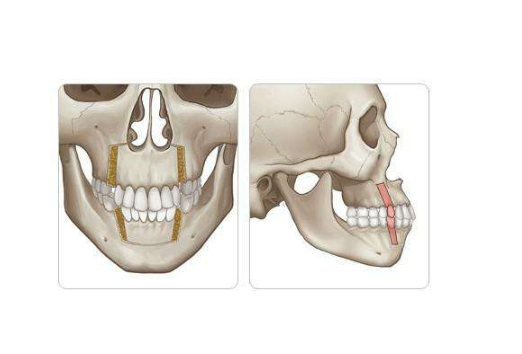

A:牙頜畸形是在兒童生長發育過程當中,由於遺傳、疾病、內分泌障礙以及營養不良、功能紊亂、口腔不良習慣、替牙障礙,還有其他因素的影響,導致牙頜面畸形,如牙齒排列不齊、上下牙弓咬合關係異常。頜骨大小形態位置異常、面部畸形等,稱為錯頜畸形,簡稱錯頜。……

A:俗稱的齙牙是上頜牙齒及上頜骨凸出,會影響咀嚼和發音,還會造成面部不協調不美觀,不同類型的齙牙矯正也不盡相同。對於生長發育期的兒童齙牙,骨骼發育具有很強的可塑性,可通過佩戴活動性矯治器對頜骨進行矯形治療。對於成年人,輕微的齙牙多因單純牙齒前突……

A:齙牙是一種容貌特徵,表現為門牙前突,導致齙牙的原因很多,通常以遺傳因素為主,另外在孩子的牙齒髮育過程中,有可能是因為發育畸形所造成齙牙。出現齙牙的時候,可以通過矯正的方式改善,這種矯正方式,越早會越好,通常有傳統的下顎畸形矯正,這種矯正方式……

A:牙頜畸形分因先天性遺傳因素造成和後天環境因素造成兩種,表現為頷骨、顱面錯位排列不齊形成畸形。建議可先去醫院口腔科拍取牙片,根據牙頜畸形情況制定治療方案,一般,常規的矯正方法有:傳統鋼絲矯正、陶瓷自鎖矯正、舌側隱形矯正和全透明隱形較正等,未成……